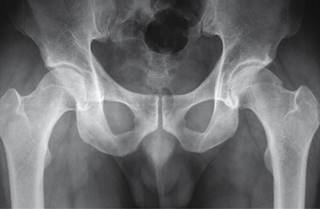

Masculino de 36 años de edad, profesionista, sin antecedentes de importancia, con dolor inguinal de un año de evolución, que se exacerba posterior a juego de balompié, obligándolo a suspender la actividad. A la exploración dirigida, postura y marcha sin alteraciones, dolor a la exploración de articulación coxofemoral durante la rotación interna y aducción con flexión de cadera a 90o, al igual que durante abducción con cadera en posición neutra. En radiografía anteroposterior de cadera se observa anormalidad de fémur izquierdo en la unión cabeza cuello, correspondiendo a pinzamiento femoroacetabular tipo leva (Figuras 1 a 3).

Figura 1: Radiografía anteroposterior de pelvis que muestra alteración de la unión de la cabeza con el cuello femoral izquierdo.